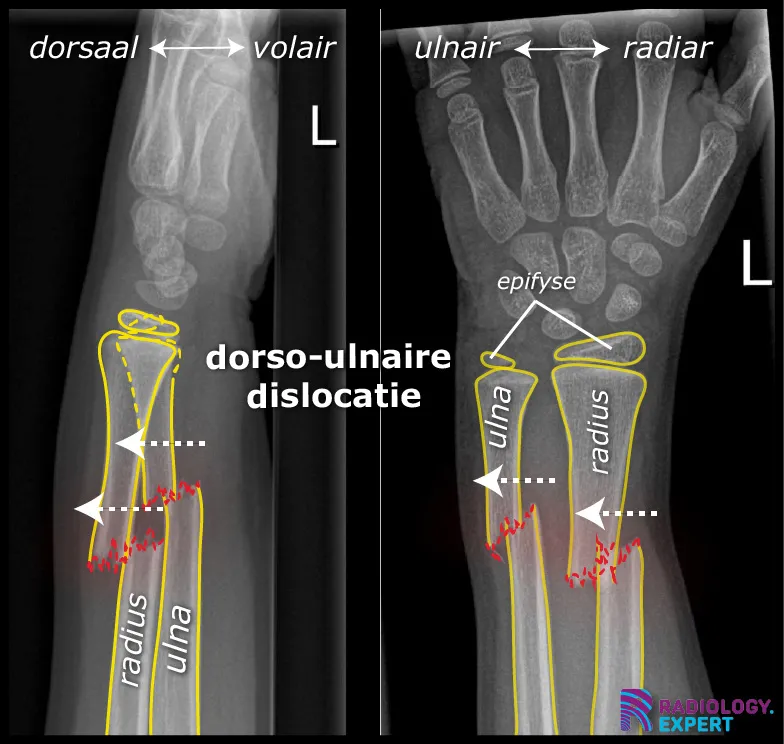

Figuur 1. Laterale en anterior-posterior opname van de linker onderarm/pols. Een kind (9 jaar oud) met distale radiusschacht & ulnaschacht fractuur. Beide tonen een dorso-ulnaire dislocatie over circa een schachtbreedte.

Klik op afbeelding om overlay te zien